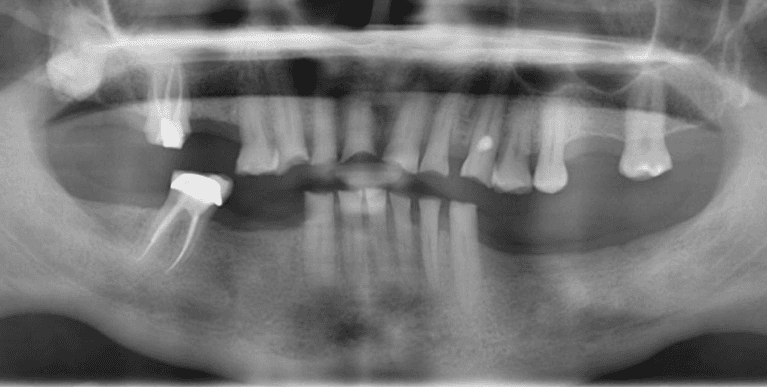

Upper & Lower, All on 4 fixed implant teeth with finals. Patient went home with temp fixed teeth the same day.